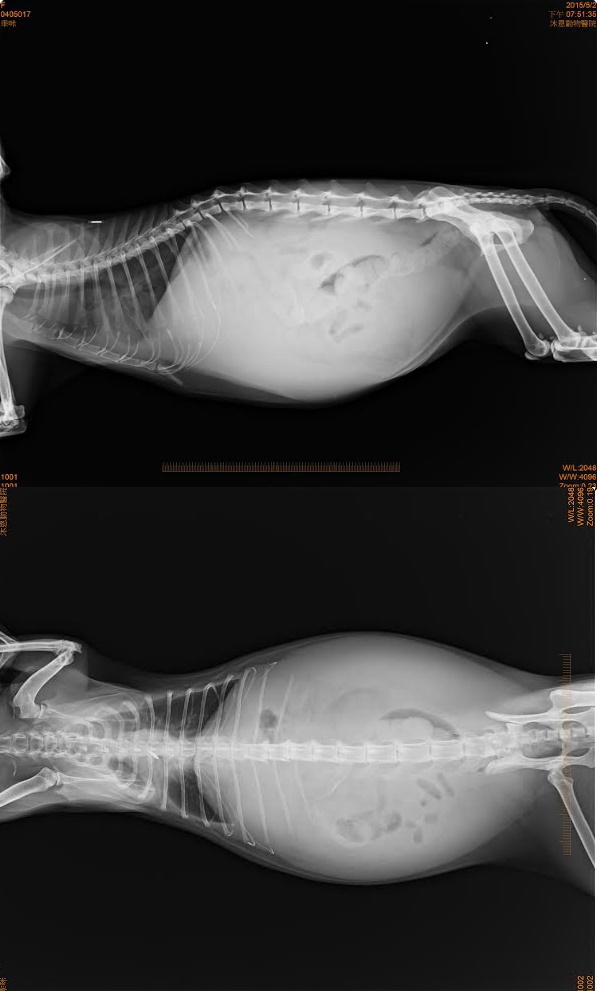

醫生觸診懷疑腹部有積水,照了超音波後確定有腹水,並抽取一管送驗、並做了血檢,已先拿幾日口服抗生素投藥,待化驗結果出爐才能做進一步的治療,這部分醫療費用由李姐支付,5/2轉院至協會配合動物醫院進行更詳細的檢查,血檢白血球3萬8,有感染的狀況,超音波檢查腹腔有腹水,檢驗膽汁酸排除肝門脈分流的問題,看診完李姐將貓咪帶回照顧,一方面可以多陪陪貓,一方面可以節省醫療費用,兩天後回診胸腹水產生速度很快,貓咪呼吸變得比較急促,鎮靜抽腹水,以期能減輕不適,並將腹水送冠狀病毒檢驗及細菌培養,先取藥一周,5/8日檢驗報告灌狀病毒核酸陽性反應,李姐的內心也很糾結,病程表現並沒有很符合一般冠狀病毒發病,且不排除同時有別的問題腫瘤與肝衰竭,醫師認為是腫瘤與冠狀病毒同時發病,目前精神食慾穩定但因為胸腹水目前出來的速度算快,預計每週都需要麻醉抽胸水,這會是比較大的醫療費用,該繼續治療還是放手,看著乖咪持續服用藥物還能夠大口大口吃飼料罐頭,又捨不得一輩子在外流離失所,終於在老年得到一個家的乖咪,就這樣離開,選擇持續治療讓這老孩子可以終老,每周固定回診拿藥抽胸腹水,乖咪過了兩個月的快樂日子,6/25日乖咪出現嚴重貧血狀況,醫師懷疑可能是腫瘤破裂導致出血,建議輸血爭取時間治療,在很臨時的情況下找到幾個熱心貓有的幫忙,順利配對為乖咪輸血,很可惜最後乖咪還是沒有度過,但這兩個月可能是他一生中最能安心睡覺的時候,不用躲避野狗追咬還有人類的驅趕,有吃不完的乾乾還有罐頭,不用日曬雨淋,還有他最愛的媽媽陪在身邊,這一生足以,李姐送走了乖咪,負擔了最後一程火化費用,已經負擔很重,一隻被好好照顧的街貓能夠享壽10年,這中間一定是付出很多心力,惟有細心觀察下才知道乖咪的變化,能及時陪伴他最後一段,李姐餵養的貓都很親他,很多傷病老殘貓都帶回照顧安置,家中也是大爆滿的狀況,每天在外辛苦餵貓,兼差賺錢多買一些飼料罐頭,就是希望這些毛孩子能吃飽一點能度過寒冬,有體力躲避危險,沉重的負擔還希望各位能夠幫忙乖咪。